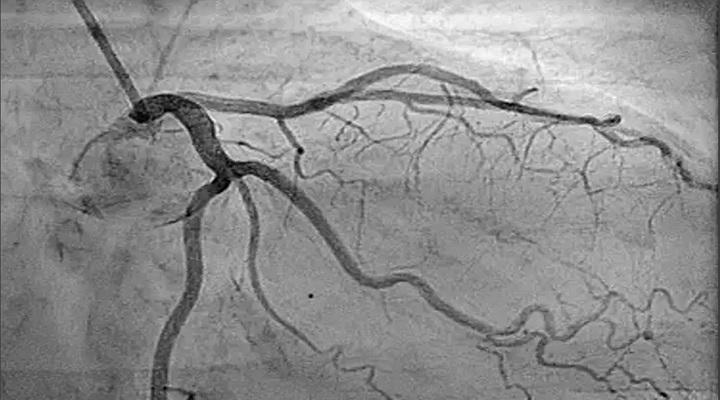

- آنژیوگرافی (کاتتراسیون قلبی): در این تست، لولههایی به درون شریانهای کرونری فرستاده میشوند تا این بیماری را ارزیابی یا تأیید کنند. این آزمایش اصلیترین تست برای تشخیص بیماری عروق کرونر است.